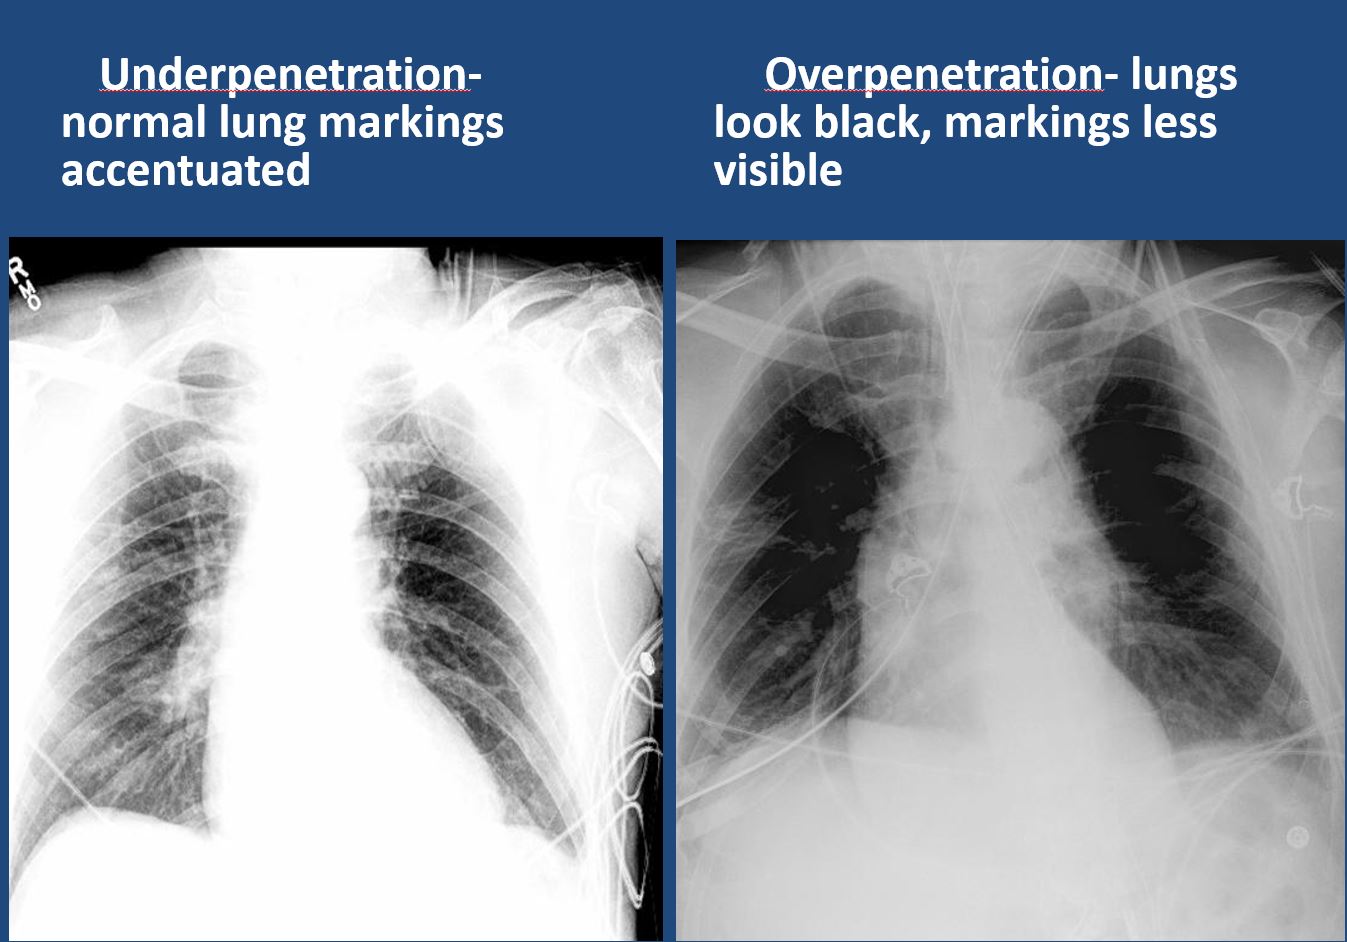

|

The exam is technically correct, and is not expiratory, is not rotated, nor over or under penetrated, nor limited by overlying structures or soft tissues, body habitus, patient positioning, or motion. |

yes | NA |